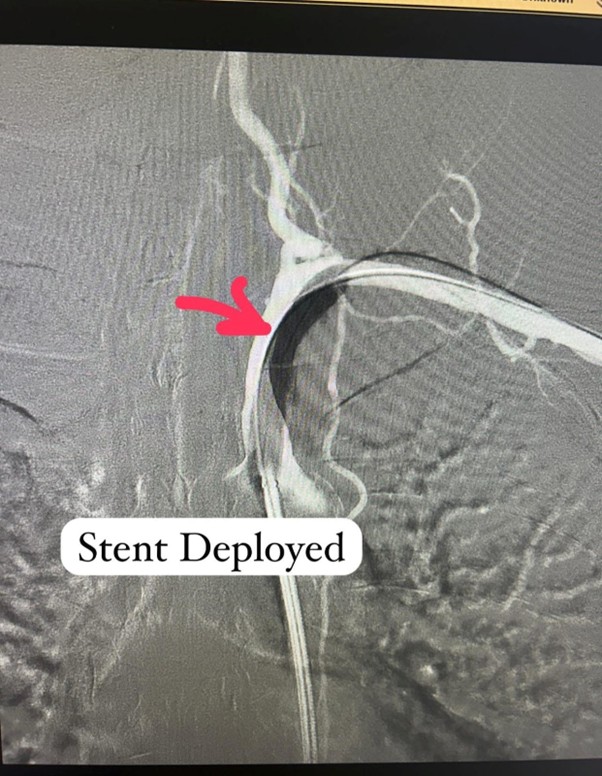

After a few weeks of medical therapy, a repeat CT Angiography showed partial recanalization of the previously occluded subclavian artery, indicating a positive response to treatment. To further define the anatomy and plan intervention precisely, Digital Subtraction Angiography (DSA) was performed. Based on these findings, Dr. Ingle successfully carried out a subclavian artery angioplasty, restoring critical blood flow to the affected limb and reducing future neurological risk.